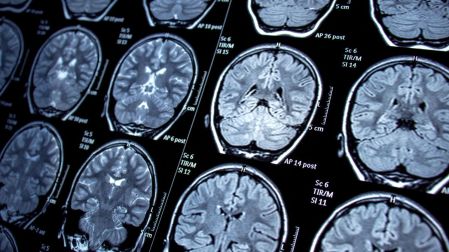

La encefalitis es una inflamación del tejido cerebral que puede presentarse durante o poco después de una infección viral, incluido el sarampión. A diferencia de los síntomas más conocidos —como fiebre, tos o erupciones en la piel— esta complicación afecta directamente al sistema nervioso central.

Cuando se desarrolla encefalitis, el paciente puede experimentar confusión, convulsiones, pérdida de conciencia, coma e incluso la muerte. En quienes sobreviven, existe el riesgo de secuelas permanentes, como problemas de aprendizaje, alteraciones motoras o dificultades cognitivas.

En el caso del brote de Carolina del Sur, autoridades sanitarias confirmaron que algunos niños hospitalizados por sarampión desarrollaron inflamación cerebral. De acuerdo con especialistas citados por Scientific American, una vez que el cerebro se inflama, el daño puede avanzar con rapidez, lo que vuelve crucial la detección temprana y la atención médica inmediata.